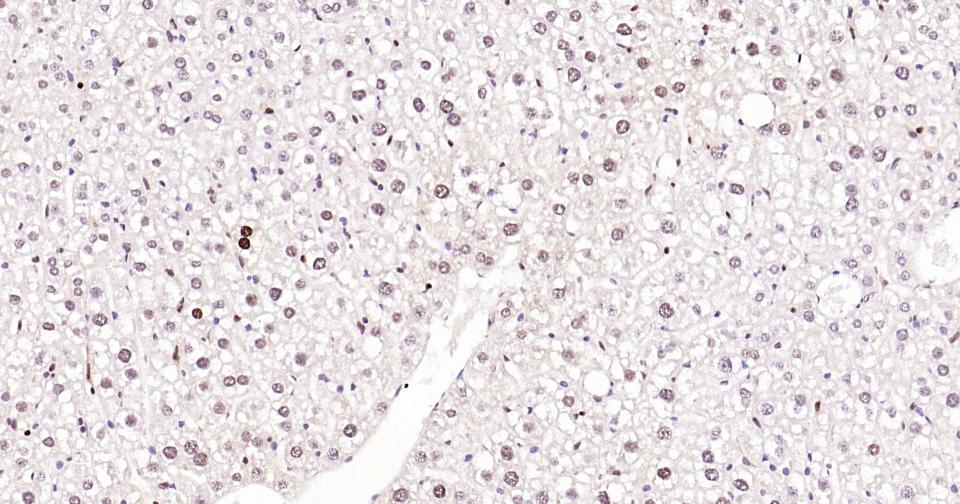

| WB, IHC-P, IHC-F, IF |

| Dilution | WB=1:500-2000,IHC-P=1:200-800,IHC-F=1:200-800,IF=1:200-800,Flow-Cyt=1 µg/Test |

| Background Descriptions | Proliferating cell nuclear antigen (PCNA) is a 28kDa nuclear protein associated with the cell cycle, a nuclear protein vital for cellular DNA synthesis. Proliferating cell nuclear antigen was originally identified by immunofluorescence as a nuclear protein whose appearance correlated with the proliferate state of the cell. PCNA is required for replication of DNA in vitro and has been identified as the auxiliary protein (cofactor) for DNA polymerase delta. The anti-PCNA antibodies react with the nuclei of proliferating cells. PCNA is essential for cellular DNA synthesis and is also required for the in vitro replication of simian virus 40 (SV40) DNA where it acts to coordinate leading and lagging strand synthesis at the replication fork. The PCNA protein may fulfil several separate roles in the cell nucleus associated with changes in its antigenic structure. |